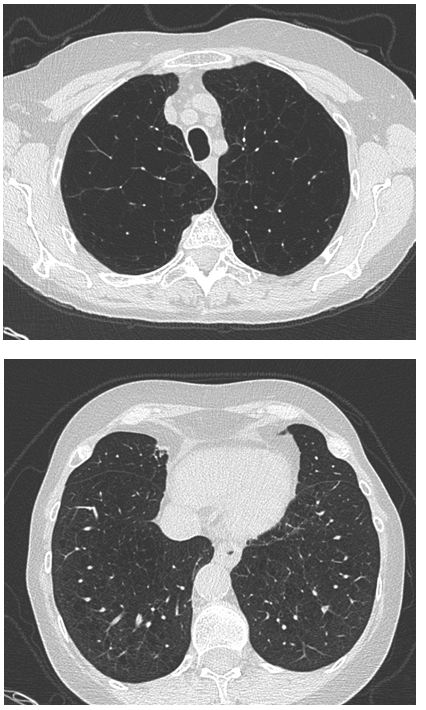

Figure 1.2: High Resolution Computed Tomography (CT) of the Chest - Demonstrating severe changes of upper lobe predominant pulmonary emphysema.